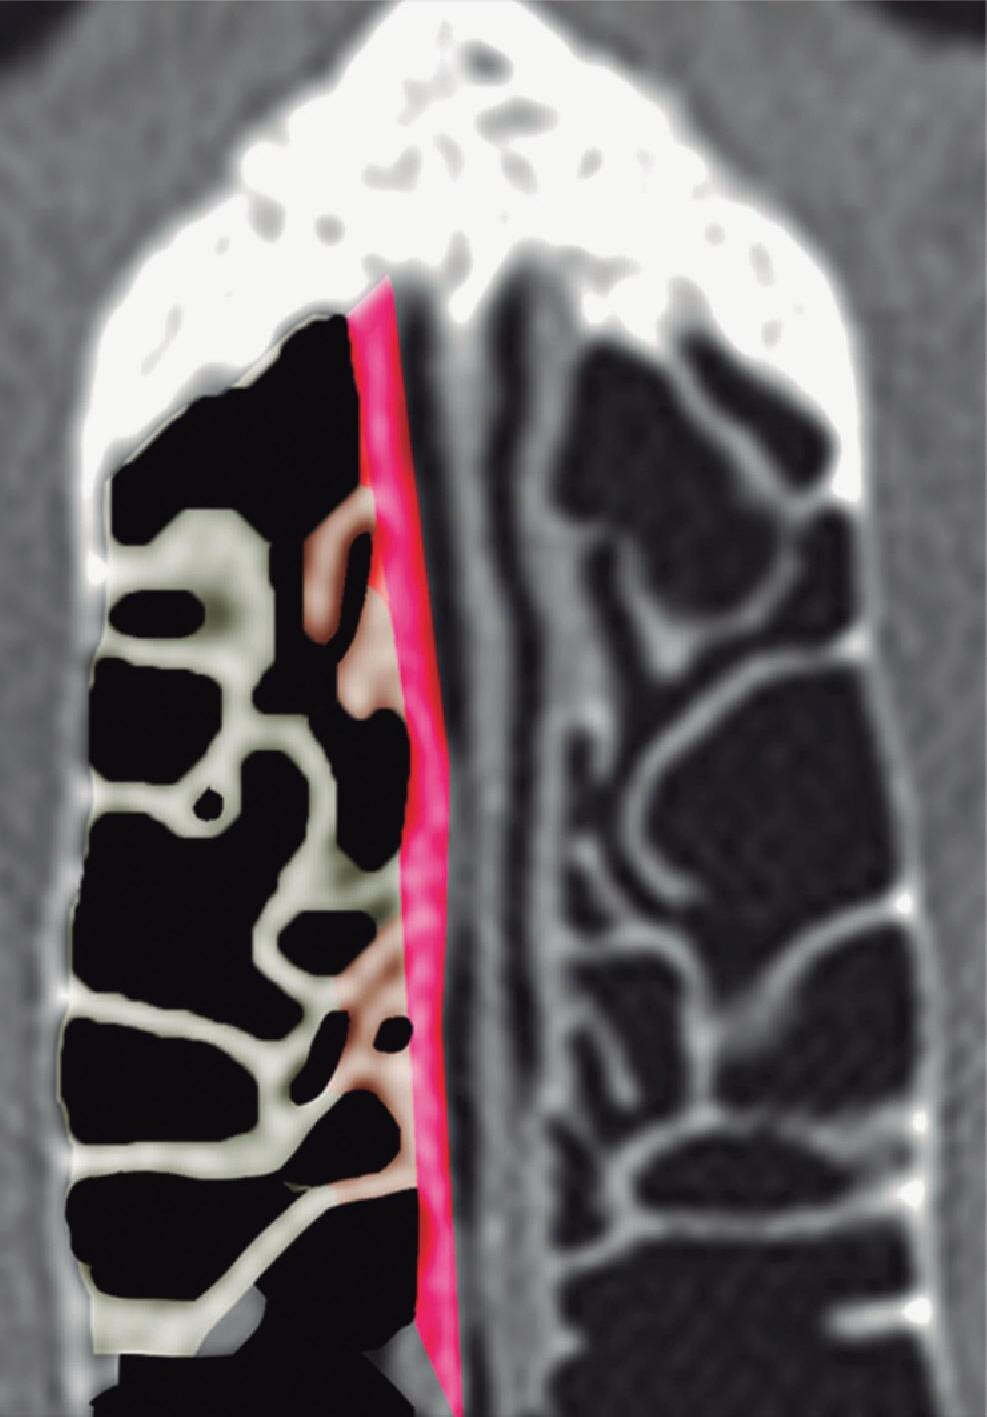

Fig. 1-20. Reconstrução tridimensional de TC demonstrando a lamela basal situada posteriormente à bulha etmoidal, acoplada à parede medial da órbita, fechando a câmara anterior: verde – concha média; vermelho – bulha etmoidal; amarelo – parede medial da órbita; lilás – processo uncinado.

Posterior à bulha etmoidal encontra-se a principal estrutura que fixa a concha média na órbita e na base do crânio: a lamela basal. Esta lamela, como a própria concha média, é oblíqua em relação à lâmina papirácea tanto no sentido anteroposterior como no superoinferior e delimita posteriormente a câmara anterior.